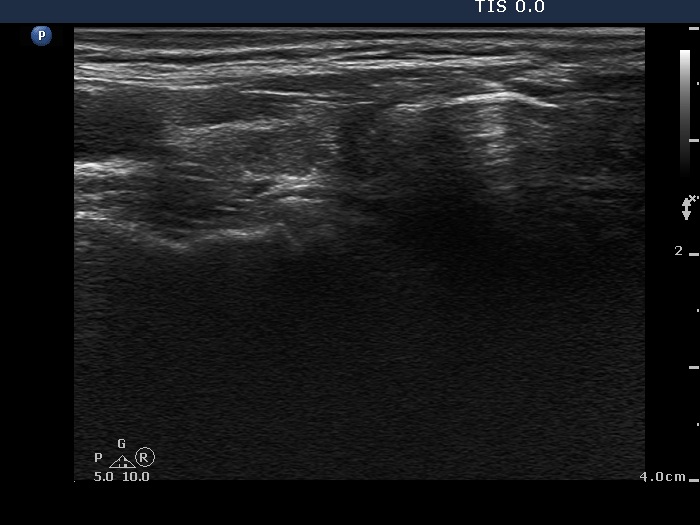

Clinical presentation: A 55-year-old woman was referred for aspiration cytology. She has a right lobectomy 10 years ago. At that time, a relatively small cystic nodule was already in the left lobe which was not operated. She noticed a lump in the left thyroid several weeks before the present examination.

Palpation: an elastic nodule in the left lobe.

Ultrasonography. There was no parenchyma in the right the thyroid bed. The left lobe was minimally hypoechogenic and had a large, multichambered cystic nodule. There were both hyperechogenic lines and granules within the dorsal wall of the cystic areas. The solid part was moderately hypoechogenic.

Comment. Most of the hyperechogenic figures correspond to posterior back wall enhancement. There were a few colloid crystals within the cystic fluid.